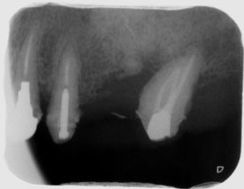

左上6番の近心に骨欠損があるため再生療法を行い、骨を回復した症例

CTにてBM2根の存在を確認しマイクロで探索。

骨吸収の改善と根尖病巣からの上顎洞の炎症も改善している。